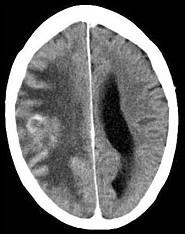

关于脑转移瘤(如图所示),瘤周围水肿属于()A.细胞性水肿B.血管源性水肿C.脑积水性水肿D.渗透性水肿E.脑缺血性水肿

问题 关于脑转移瘤(如图所示),瘤周围水肿属于()

选项 A.细胞性水肿 B.血管源性水肿 C.脑积水性水肿 D.渗透性水肿 E.脑缺血性水肿

答案 B